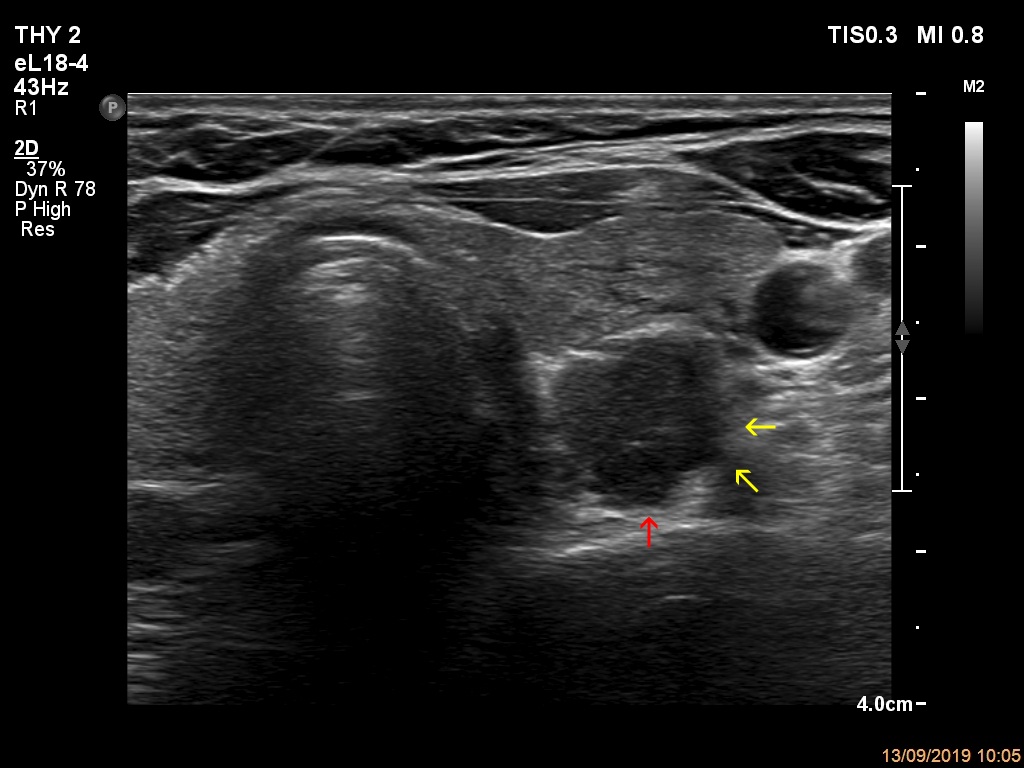

Elastography - case 2089 (ultrasonographic picture 6b)

Left lobe, another transverse view. The dorsolateral part presents spiculated margins (yellow arrows). The undulation marked with red arrow is caused by the presence of multiple lesions next to each other.